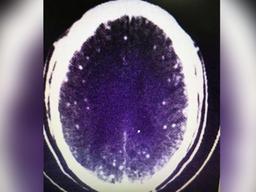

뇌에 구멍이 수십 개... 덜 익은 돼지고기 함부로 먹으면 안 되는 이유

28일, 영국 데일리메일 등 외신들은 '

신경

낭미충증

'에 걸려 사망한 인도 청년의 사연을 소개했습니다. 소년은 사고 발생 전 사타구니 근처에 통증을 호소했습니다. 이뿐만 아니라 눈이 부어오르고 두통에 시달리는 등 몸 상태가 점점 안 좋아졌습니다. 결국 일주일간 알 수 없는 고통에 시달리던 소년은 발...

‘훠궈’ 먹은 中남성 뇌에서 기생충 수백마리 발견…왜?

씨(46)가

을 진단받았다고 27일(현지 시간) CNN이 중국 저장대 연구결과를 인용해 보도했다. 주 씨는 약 한 달 전 돼지고기와 양고기를 넣어 만든 훠궈를 먹었다. 그로부터 며칠 후 어지럼증과 두통을 겪었다. 또한 잠을 자다 간질과 비슷한 발작 증상을 일으키는 등 병세가 악화했다. 주 씨의...